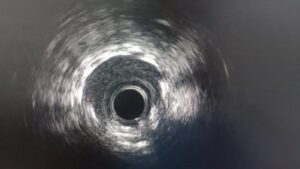

IVUS Revealed the True Calcium Burden

Following atherectomy, IVUS was performed, and this provided critical insight into the lesion morphology.

The imaging showed extensive severe calcium with mixed morphologies, confirming that the lesion was not only heavily calcified but also structurally complex. This is exactly why intracoronary imaging is so important in advanced calcium cases.

Angiography can suggest calcium. IVUS defines it.

In this case, IVUS guided the next decision: further lesion optimization was still necessary.

Final Result: Good Stent Expansion on IVUS

After stent implantation, post-PCI IVUS confirmed good stent expansion.

This is one of the most important takeaways from the case.

In severe calcific disease, the procedure should not be judged by angiographic appearance alone. The true procedural endpoint is not merely placing stents, but achieving:

• proper stent expansion

• good apposition

• full lesion coverage

• optimized vessel preparation before final deployment

That is why imaging remains central in modern complex PCI, particularly in calcified lesions and CTOs.

Good expansion in this setting reflects the value of the entire procedural sequence:

wire escalation, failed crossing attempts, atherectomy, imaging-guided assessment, additional scoring balloon modification, supported stent delivery, and final IVUS optimization.